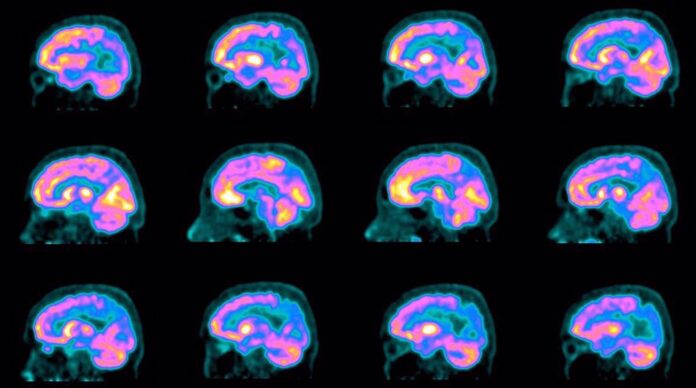

تہران (مشرق نامہ) – ایرانی جوہری سائنسدانوں نے ایک ایسا ریڈیو فارماسیوٹیکل تیار کر لیا ہے جو الزائمر کی بیماری کو علامات ظاہر ہونے سے بیس سال قبل ہی تشخیص کر سکتا ہے، جس سے بروقت مداخلت اور علاج کے امکانات میں نمایاں اضافہ ہوگا۔

منگل کو جاری رپورٹ کے مطابق، یہ نیا ریڈیو فارماسیوٹیکل، جسے فلوربیٹا پیر کہا جاتا ہے، نہ صرف بیماری کی ابتدائی پیتھالوجیکل علامات کی نشاندہی کرتا ہے بلکہ مرض کی رفتار کو کم کرنے کے لیے زیادہ ہدفی اور مؤثر علاج کے طریقے بھی ممکن بناتا ہے۔

ایک ایرانی جوہری سائنسدان نے وضاحت کی کہ فی الحال الزائمر کا کوئی علاج موجود نہیں، لیکن اس کی پیش رفت کو سست کیا جا سکتا ہے۔ انہوں نے کہا کہ حال ہی میں تیار کیے گئے ریڈیو فارماسیوٹیکلز میں سے ایک خاص طور پر الزائمر کی ابتدائی تشخیص کے لیے ڈیزائن کیا گیا ہے اور یہ بیماری کے آغاز کی پیش گوئی دو دہائیاں پہلے تک کر سکتا ہے۔

ایک مخصوص کیس اسٹڈی میں، 56 سالہ مریض کو، جس میں یادداشت کی کمی کے آثار تھے، انجیکشن کے بعد امیجنگ کرائی گئی، جس کے نتائج میں مثبت کلینیکل بہتری اور اعصابی صحت میں واضح پیش رفت دیکھی گئی، جس سے قبل از وقت تشخیص کی افادیت ثابت ہوئی۔

بڑی عالمی فارماسیوٹیکل کمپنیوں کے ساتھ تعاون میں مشکلات کے باوجود، ایرانی سائنسدانوں نے فلوربیٹا پیر کی پہلی مقامی خوراک تیار کرنے میں کامیابی حاصل کر لی۔ اب تک 80 مریض اس ریڈیو فارماسیوٹیکل سے مستفید ہو چکے ہیں اور نیوکلئیر میڈیسن کے ماہرین نے الزائمر کی قبل از وقت تشخیص میں شاندار نتائج کی اطلاع دی ہے۔